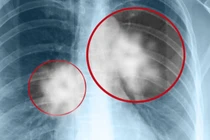

Phát hiện sớm nấm phổi xâm lấn để giảm nguy cơ tử vong Sức khoẻ 360 17/12/2025 07:17 Bệnh nhân cao tuổi mắc nấm phổi do Candida albicans cần theo dõi sát để tránh biến chứng nặng, điều trị phù hợp giúp cải thiện khả năng sống còn.